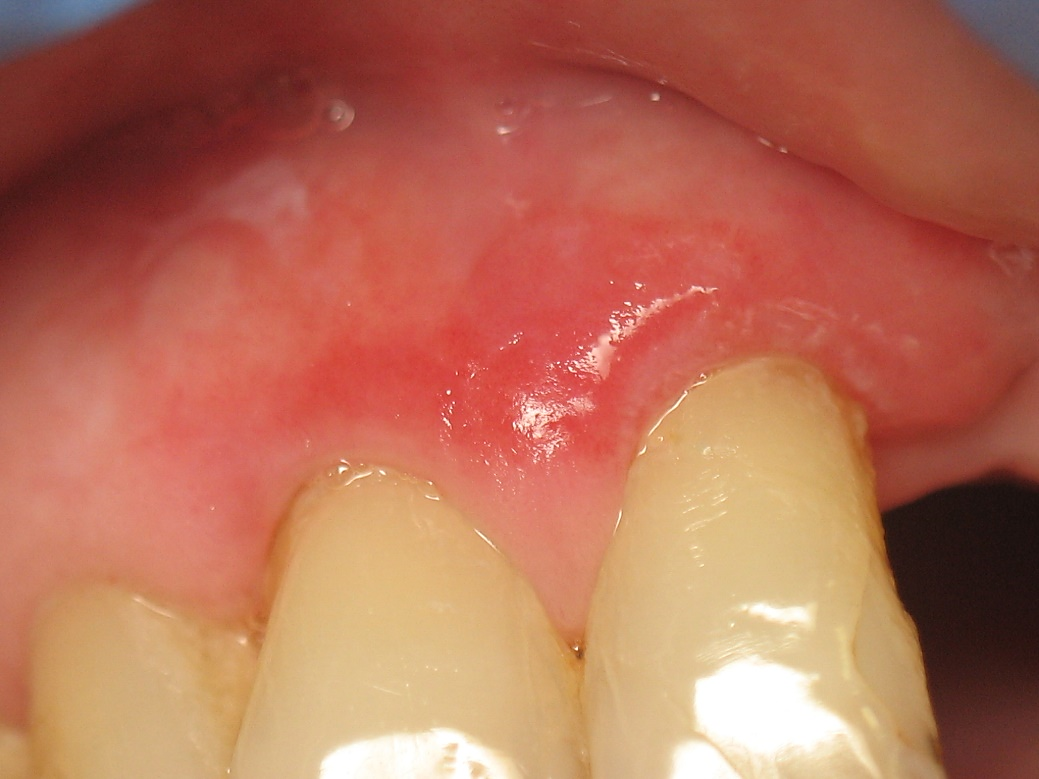

Подавляющее большинство (17; 65,4 %) пациентов с проявлениями ДГ на фоне КПЛ жаловались на сильную боль, жжение, сухость и чувство обожженной десны, неприятный запах изо рта, создающие серьезные проблемы при приеме пищи, разговоре, активной коммуникации с окружающими. Часть пациентов беспокоил необычный ярко-красный «лакированный» вид слизистой десен в зоне улыбки, сопряженный с симптомом канцерофобии. При объективном обследовании на вестибулярной поверхности десны в области передних (верхних и нижних) секстантов обнаруживали множественные мелкие или крупные участки десквамации эпителия, имеющие ярко-красную окраску на фоне разлитого отека и маргинальной эритемы. Клинические симптомы соответствовали среднетяжелой степени тяжести ДГ (рис. 2). Типичные проявления тяжелого ДГ – с интенсивным спонтанным и индуцированным болевым, сенсорно-парестетическим и геморрагическим симптомами, образованием на вестибулярной поверхности десны в зоне передних зубодесневых секстантов обширных кровоточащих сливных эрозий, пузырных элементов, требующих проведения теста(ов) Никольского. Легкие стадии ДГ и его генерализованные формы с эрозированием вестибулярной десны 3 секстантов и более у больных с КПЛ СОР не наблюдали. Симптом Никольского у этих больных был отрицательным, аллергоанамнез, как правило, не отягощен, однако у 4 пациентов (3 женщины и один мужчина), предъявляющих жалобы со стороны слизистой половых органов, по результатам проведенного гинекологического и урологического обследования были выявлены эрозивные поражения слизистых половых органов в виде десквамативного вагинита и уретрита неинфекционной природы. Наличие специфической инфекции мочеполовых органов у 3 пациенток по результатам лабораторной диагностики было исключено, и, по показаниям лечащего гинеколога, было проведено гистологическое исследование, по результатам которого в строме, суббазально выявляли диффузные, преимущественно лимфоплазмоцитарные инфильтраты – типичный гистологический симптом КПЛ. Для подтверждения диагноза вульво-вагинально-гингивального синдрома врачом-стоматологом была проведена биопсия десны (вне прямой зоны поражения), результаты которой подтвердили диагноз этого синдрома как проявления КПЛ слизистой половых органов и СОР: в эпителии десны выявляли гипер- и паракератоз, акантоз, геморрагии; фокальное расслоение базальной мембраны, явления очаговой баллонирующей дегенерации; субэпителиально – отек и диффузную лимфоплазмоцитарную инфильтрацию, с участками проникновения инфильтратов в нижние слои базальной мембраны.

Рис. 2. Больной К., 33 года. Диагноз: десквамативный гингивит средней степени тяжести как моносимптом у пациента с КПЛ СОР